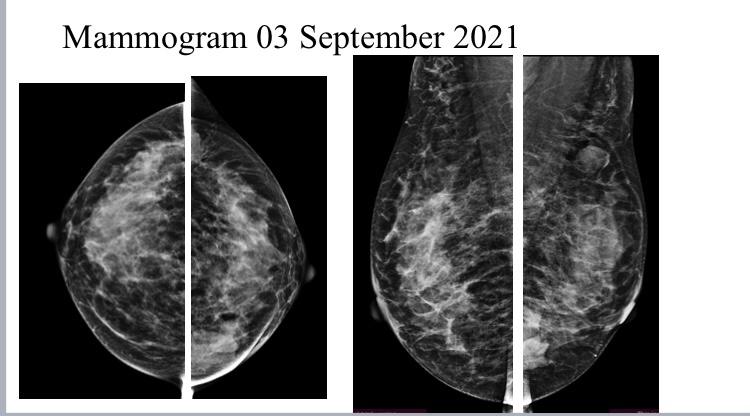

A 55 years old female came for screening mammogram....

Read More